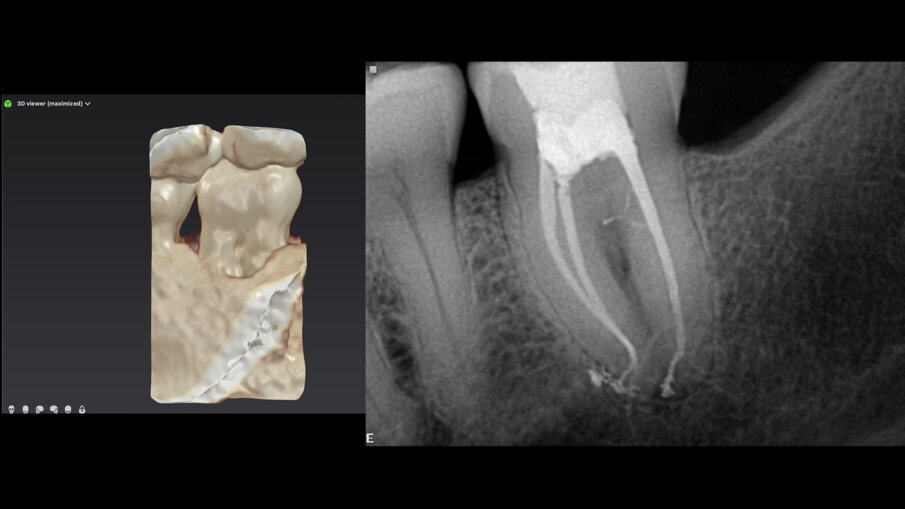

Ovaj pacijent je hitno došao zbog oštrog bola u drugom maksilarnom molaru. Ovo je potvrđeno kliničkim pregledom. Napravljen je standardni radiograf (Sl. 1), koji pokazuje veoma složenu anatomiju i kalcifikovanu pulpnu komoru. Istorija ovog zuba, kako je opisao pacijent, bila je da je na njega postavljen inlej i nakon nekog vremena se pojavila nelagodnost koja je trajala nekoliko godina bez lečenja. Na pregledu mu je rečeno da je sve u redu.

Tražio sam da se uradi i-CAT skeniranje kako bih bolje razumeo šta se dešava. Proučavajući horizontalni prikaz 3D slike, jasno se može videti nivo kalcifikacije u pulpnoj komori u poređenju sa pulpnom komorom prvog molara (Sl. 2).

Endodontski režim u novom softveru DTX Studio Clinic omogućava dodavanje mnogih pogleda i preseka i podešavanje debljine preseka kako bi se proverio nivo kalcifikacije. Dodatna prednost je što omogućava praćenje unutrašnje anatomije korena, pojedinačno i zajedno. Prilikom praćenja kanala korena, boja se može izabrati za svaki kanal. Ovo je od velike koristi za vizuelizaciju unutrašnje anatomije (Sl. 3).

Pomoću ovog softvera može se vizualizovati 3D model zuba sa kanalima ucrtanim sa njihovim približnim radnim dužinama, dajući nam predstavu šta da očekujemo (Sl. 4). Na primer, u ovom slučaju, prosečna radna dužina je bila oko 27 mm za ovaj drugi maksilarni molar sa četiri kanala i ovakvom anatomijom — ja ove slučajeve zovem dupli espreso jer su mali izazov. Na primer, distalni kanal je imao oštru krivinu poput kuke na vrhu. Svi ovi podaci mogu pomoći u odabiru sekvence endodontskih turpija za oblikovanje i čišćenje sistema kanala korena. Traverse i ZenFlex turpije (Kerr Dental; Sl. 5) su korišćene za oblikovanje kanala. U distalnom korenu, turpija 30/.04 nije korišćena u poslednja 2 mm, kako bi se izbeglo bilo kakvo deformisanje ove oblasti. Irigacija je obavljena prema Sleimanovoj sekvenci irigacije (objavljeno u roots magazinu 1/2014). 3D obturacija kanala izvedena je sa Elements IC obturacionim sistemom (Kerr Dental; Sl. 6).

Sl. 1: Rendgen snimak pre operacije, koji pokazuje veoma složen sistem korenskih kanala i kalcifikovanu pulpnu komoru

Sl. 2: Horizontalni presek preuzet sa i-CAT skeniranja (DEXIS) koji pokazuje totalnu kalcifikaciju otvora kanala korena na nivou cementno-gleđnog spoja, u poređenju sa prvim molarom

Sl. 3: Endodontski režim u DTX Studio Clinic koji prati anatomiju kanala i daje približnu radnu dužinu u različitim bojama za svaki kanal

Sl. 4: 3D rekonstrukcija kanala u različitim bojama, koja prikazuje detaljnu dužinu segment po segment za svaki kanal